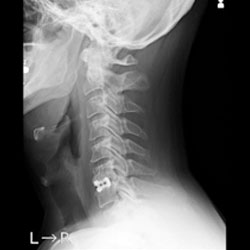

頚椎疾患

頚椎は頭部を支える骨で、頚椎の中には脊髄が通っています。

この頚椎で起こる様々な疾患が頚椎疾患で、主なものとして頚椎症性神経根症や頚椎症性脊髄症、頚椎椎間板ヘルニア、後縦靱帯骨化症などがあります。

頚椎症とは、加齢による椎間板の変性が原因で背骨が変形し、脊柱管や椎間孔が狭窄してしまう状態を言います。

脊柱管や椎間孔の狭窄により神経根や脊髄が圧迫され、肩や腕、手などに痛みや痺れなどの症状が現れます。

検査と診断

問診や診察などで頚椎後縦靭帯骨化症が疑われる場合には、まずレントゲン検査を行い、必要に応じてCT検査・MRI検査を行います。